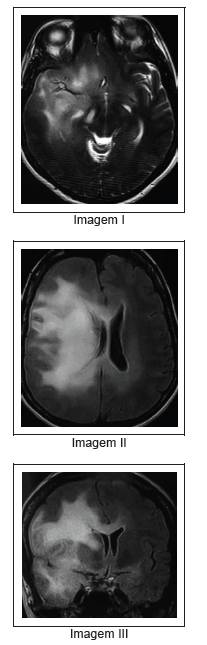

Uma senhora de 45 anos de idade, previamente sadia, notou leve desvio da rima labial para a direita há um mês. Há dois dias, vêm ocorrendo episódios de curta duração, que se iniciam com sensação de odor desconhecido, seguido por sensação de desorientação, o que faz deixar de reconhecer ambientes familiares como sua própria casa. Ocorrem cerca de sete episódios ao dia. Ela continua realizando seus afazeres domésticos rotineiramente. Não apresentou febre, tosse, dor abdominal, alterações urinárias ou fecais. O exame clínico mostra paciente consciente, orientada, sem oftalmoplegias, com fundo de olho normal. Há leve hemiparesia esquerda que envolve a hemiface e MSE. Não há sinal de Babinski. Os exames de sangue, incluindo hemograma, VHS, PCR, eletrólitos, glicose, ureia, transaminases, radiografia de tórax, foram normais. Uma ressonância magnética de crânio mostrou os achados a seguir.

Os dados clínicos associados aos dados de neuroimagem apontam para o diagnóstico de